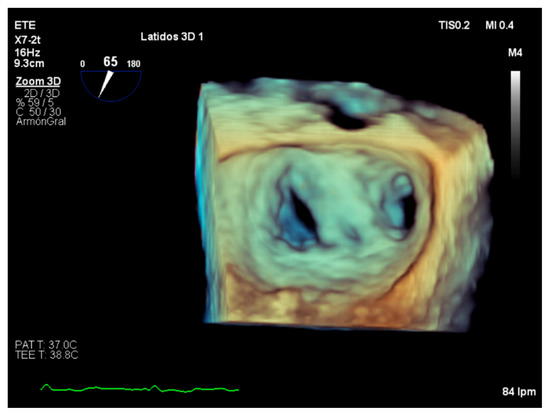

4. Assessment of Suitability of Valvular Repair

5. Role of Intraoperative Echocardiography